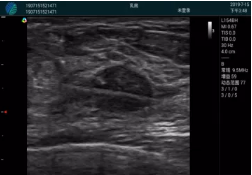

腺體內部清晰顯示一低回聲塊影,形態(tài)不規(guī)則,邊界模糊,邊緣呈毛刺狀,內部見砂礫樣鈣化

M20引導下穿刺活檢術

M20引導下平面內穿刺取出的腫塊組織